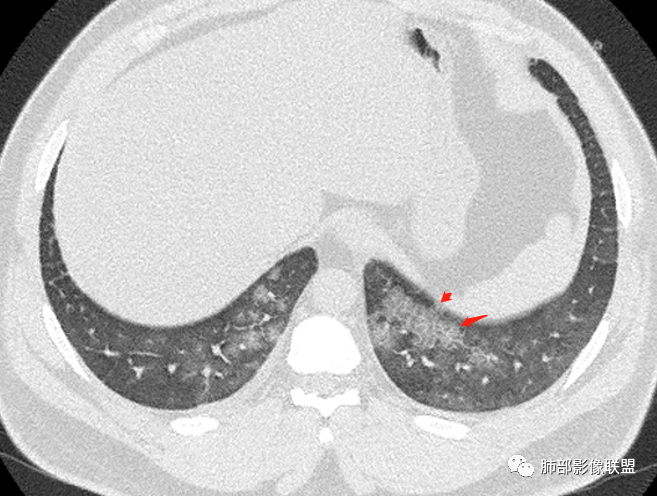

年轻男性,肾功能不全,未提感染症状,ct双侧弥漫性小叶中心性磨玻璃影,双下肺为著,考虑肺含铁血黄色沉着症

多发GGO结节,边界清,以全小叶、小叶中心为主:

小叶间隔增厚,无明显重力趋势

转移性钙化?

有老师提出过转移性钙化

转移性钙化继发于甲旁亢和慢性肾衰

磷酸钙沉积在肺泡间隔

腺泡融合,不考虑转移性钙化

对比一下,是不符合转移性钙化

转移性钙化上叶显著,且小叶间隔增厚少见

早期可以没有,上面的文章提到60%有钙化

钙化在间质还是实质里

间质,肺泡间隔